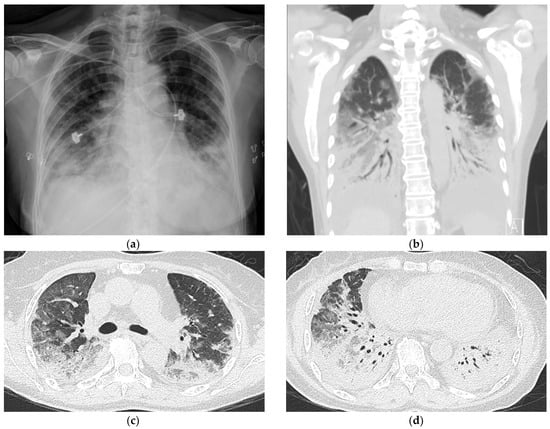

Two days before admission, she presented at our emergency department with fever, cough, and progressive dyspnea. An examination revealed that she had tachypnea and an oxygen saturation of 66% while breathing ambient air. She received oxygen therapy through a non-rebreathing mask. Her white-cell count was 12,800 per µL (reference: 4140–10,520 per µL), and her C-reactive protein was 59 mg/L (reference: <5 mg/L). Her hemoglobin, platelet, serum procalcitonin, B-type natriuretic peptide, creatine kinase, liver, and renal functions were all normal. Detailed serologic testing disclosed a positive anti-Jo-1 of 89 EliAU/mL (reference: <7 EliAU/mL) and anti-Ro52 of 3+ (reference: negative). Her rheumatoid arthritis factor, anti-La, anti-SCL-70, anti-ds DNA, anti-MDA-5, and other myositis-specific autoantibodies (MSAs) were all negative. A chest radiograph revealed consolidations in the bilateral lower lungs (Figure 2a).

After the patient was admitted to an intensive care unit, we shifted oxygen supplementation to a high-flow nasal cannula that delivered a fraction of inspired oxygen (FiO2) of 80%. Chest CT revealed consolidations and ground-glass opacities over the bilateral lungs with peripheral and lower lung zone predominance (Figure 2b–d). Sputum cultures showed no growth of bacteria, fungus or mycobacteria. Given the features of positive anti-Jo-1 and anti-Ro52, the absence of extrathoracic manifestations, and the failure to meet specific CTD criteria, a diagnosis of IPAF was made after a multidisciplinary discussion involving two pulmonologists, a rheumatologist, and a radiologist. Other diagnoses, including bacterial pneumonia, adult respiratory distress syndrome, cardiogenic pulmonary edema, and cryptogenic organizing pneumonia were further excluded based on her clinical presentations and laboratory data. Additionally, her clinical features were unable to fulfill the diagnosis of anti-synthetase syndrome based on the criteria proposed by Solomon et al. [4]. The patient received methylprednisolone pulse therapy (500 mg/day for 3 days), followed by one dose of 500 mg cyclophosphamide. On the 5th day of hospitalization, she was intubated for severe hypoxemia. She also received treatment with prone positioning and broad-spectrum antibiotic piperacillin/tazobactam (4.5 g every 8 h), and her oxygen saturation improved gradually. On the 16th day of hospitalization, she was extubated successfully and discharged on the 26th day.

Figure 2. Chest imaging upon admission to the intensive care unit (a) Chest radiograph revealed new development of bibasilar consolidations. (bd) Computed tomography scans revealed consolidations and increased ground-glass opacities over the bilateral lungs.